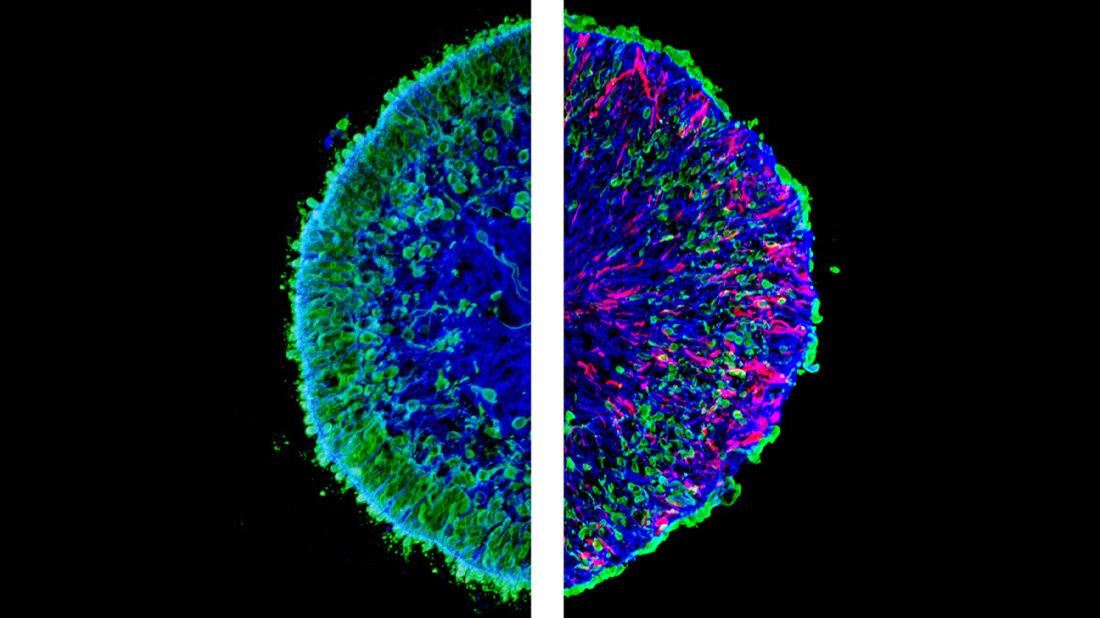

*Mikroskopische Aufnahmen von im Labor gezüchteten Mini-Netzhäuten, so genannten menschlichen Netzhaut-Organoiden. Das linke Bild zeigt einen Schnitt eines gesunden (Kontroll-)Organoids. Das rechte Bild zeigt einen Organoidschnitt mit pathologischen Veränderungen. Auf der rechten Seite ist ein sichtbarer Verlust an grüner Farbe zu erkennen, der dem massiven Verlust von Photorezeptorneuronen entspricht, die grün markiert sind. Die rote Farbe zeigt die pathologischen Müller-Glia-Zellen, die in der gesunden Kontrollgruppe nicht vorhanden sind. © Völkner et al., Nat. Comm., 2022